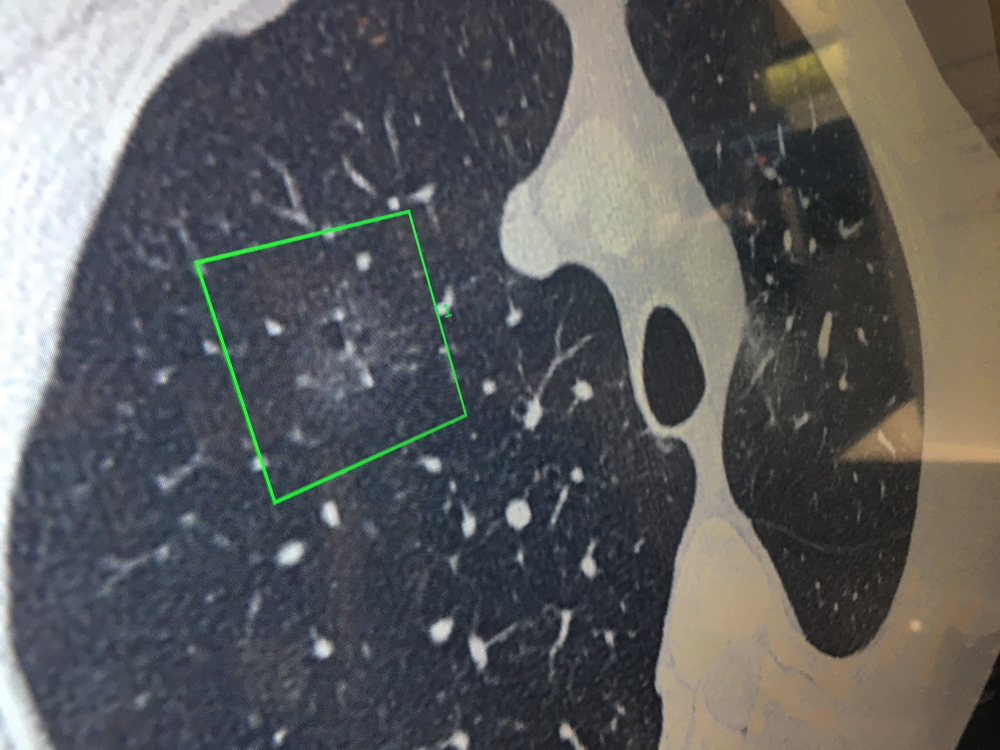

This is a lung X-ray reviewed automatically by artificial intelligence (AI) to identify a collapsed lung (pneumothorax) in the color coded area. This AI app from Lunit is awaiting final FDA review and in planned to be integrated into several vendors' mobile digital radiography (DR) systems. Fujifilm showed this software integrated as a work-in-progress into its mobile X-ray system at RSNA 2019. GE Healthcare has its own version of this software for its mobile r=ray systems that gained FDA in 2019.